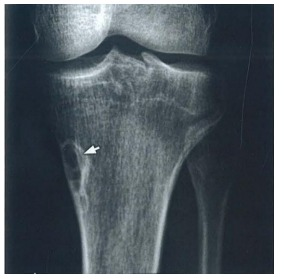

Radiografia realizada em paciente do sexo masculino de 17 anos demonstra a lesão radioluminescente com bordas escleróticas apontada pelas setas na figura. O diagnóstico CORRETO é: